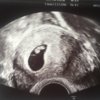

Noen med ul i uke 8 som har lyst til å dele bilde? [emoji5]

Hva ser man i uke 7/8/9 ?